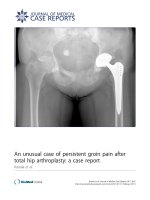

Figure 1: Radiograph of a hip spacer of a 63year old man

with late periprosthetic infection of the left hip